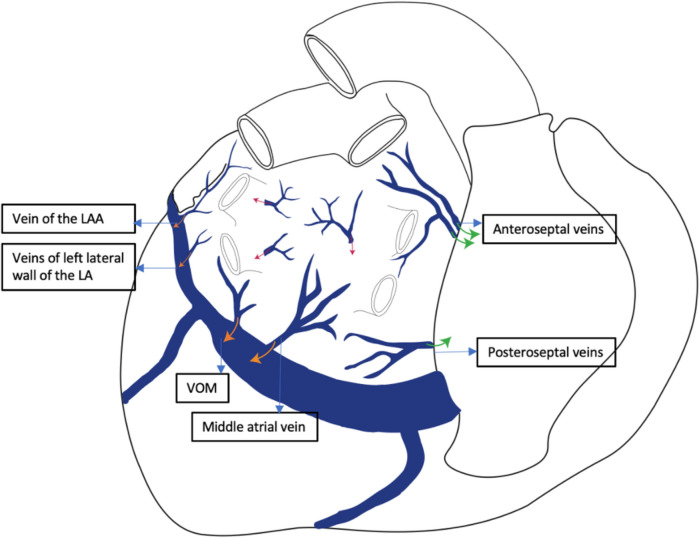

Purpose of review: This review aims to synthesize current knowledge on the angiographic anatomy of the coronary sinus and its tributaries veins, with focus on venous branches other than classical ones used in cardiac resynchronization therapy. It also presents common anatomical aspects that could impact the clinical outcome.

Recent findings: Recent advancements in the electrophysiology field, like epicardial arrhythmia mapping and ablation through coronary sinus or cardiac pacing from atypical veins requires a detailed angiographic assessment of cardiac veins. There is an increased interest for the veins coursing in the left ventricular summit (LVS) area and could potentially provide a pathway to reach the LVS arrhythmogenic foci. However, there is no consensus regarding the nomenclature and classification of these veins. This review could offer a better understanding of the coronary sinus and its tributary veins distribution, dimensions and relationship with nearby structures that could help the development of new ablation and pacing tools and strategies, with higher success rates.